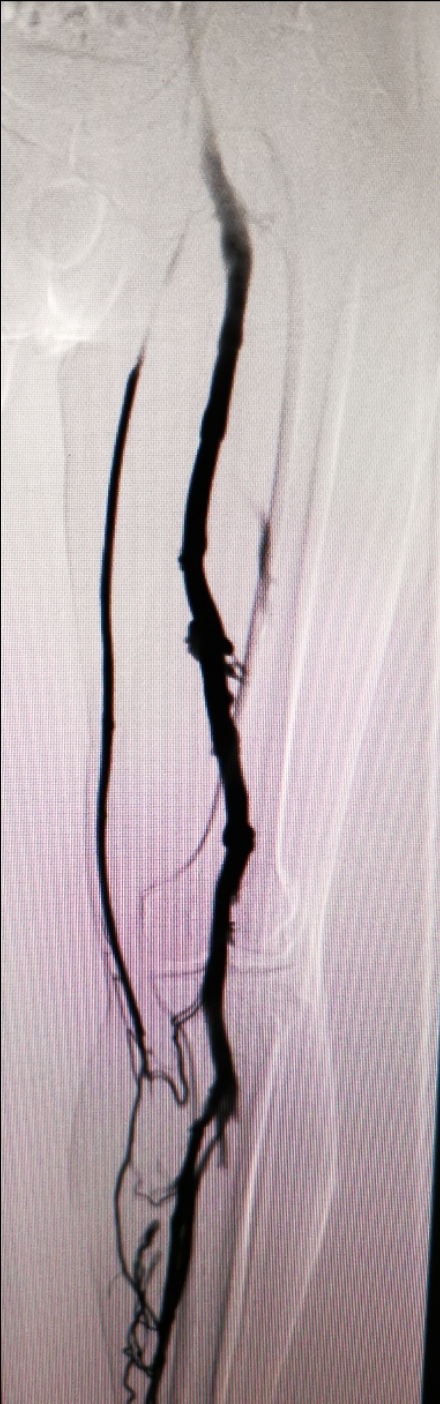

我们可以进行药物治疗和介入治疗,只要病人最近半年没有活动性出血如胃出血和脑出血,我们可以进行抗凝治疗。抗凝最大的风险是出血和血栓脱落,出血我们可以监测凝血时间,防治肺动脉栓塞,我们可以放滤器保护肺动脉。介入治疗主要是对有血栓的静脉进行血栓抽吸、球囊扩张、支架植入等。